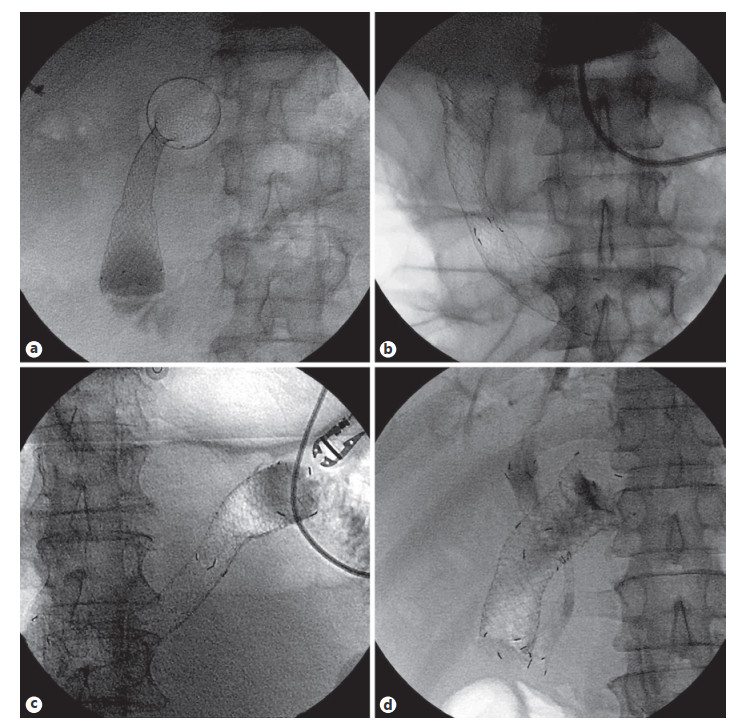

Abstract: Self-expandable metal stents (SEMSs) are frequently utilized for palliation of malignant gastric and/or duodenal outlet obstruction (GDOO). Re-establishing luminal patency with accurate SEMS positioning while limiting migration and adjacent tissue injury is an important technical consideration and aim. The duodenal HANAROSTENT® was introduced in the USA in 2019 and developed with these challenges in mind. As the first center in the USA to deploy the duodenal HANAROSTENT® in clinical practice, we herein examine our early experience with its use. Specifically, we describe 7 consecutive cases of malignant GDOO in which a duodenal HANAROSTENT® was placed for on-label use, defined as palliative treatment of malignant gastric and/or duodenal obstruction. All stents were 22 mm in diameter, with 5 being 90 mm and 2 being 120 mm in length. Technical and clinical success with duodenal HANAROSTENT® placement were achieved in all 7 cases (100%). In no case was stent adjustment required post-deployment. There were no stent-related adverse events, and no subsequent endoscopic procedures were necessary in any of the patients during a mean follow-up of 5 months (range 1–12 months). In summary, the duodenal HANAROSTENT® appears to perform well and be a promising alternative to other available duodenal SEMSs. As experience in the USA with this newly introduced duodenal SEMS grows, multicenter prospective data should be collected to better establish its relative safety and efficacy.